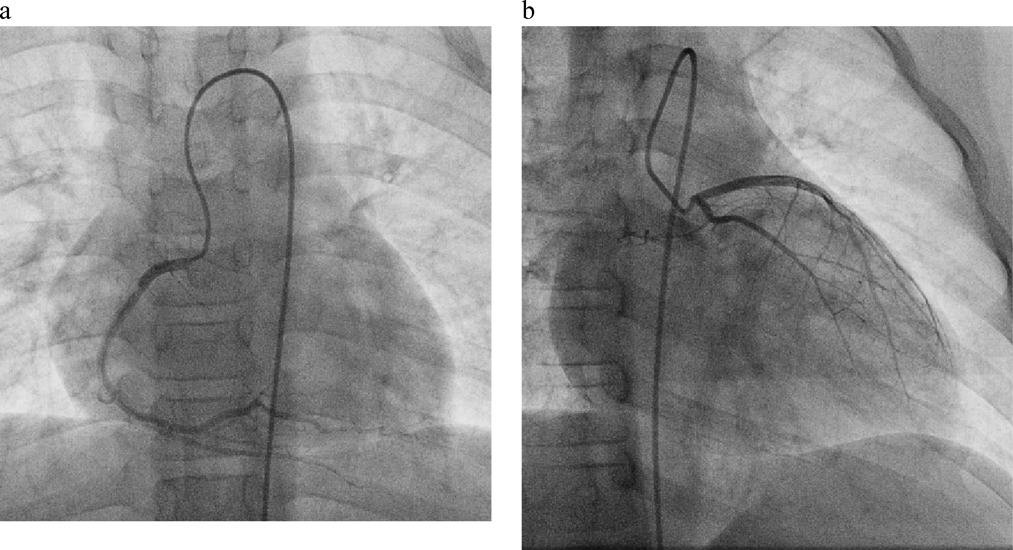

入院後2時間を経過した早朝に突然,苦悶様顔貌を伴う激しい胸痛を訴えた.直ちに行った心電図検査では,心拍数100bpm,不整脈はなく,II,III,aVF誘導で0.3 mV,V4-6誘導で0.6 mVのST上昇を認めた(Fig. 1b).心筋虚血と判断し,ニトログリセリン舌下スプレーを噴霧したところ,5分後には胸痛症状は残存していたものの,30分後には改善していた.また,心電図のST上昇も改善した(Fig. 1c).入院後7日目に心臓カテーテル検査と冠動脈造影を施行したが,右冠動脈,左冠動脈に有意な狭窄は認めなかった(Fig. 3a, b).以上より,CSAを強く疑った.その後の胸痛の訴えはなく経過し,入院後8日目に退院となった.

Pediatric Cardiology and Cardiac Surgery 37(4): 307-311 (2021)

Fig. 3 Coronary angiography

No significant stenosis was exhibited in the left or right coronary arteries. a: Right coronary angiography. b: Left coronary angiography.